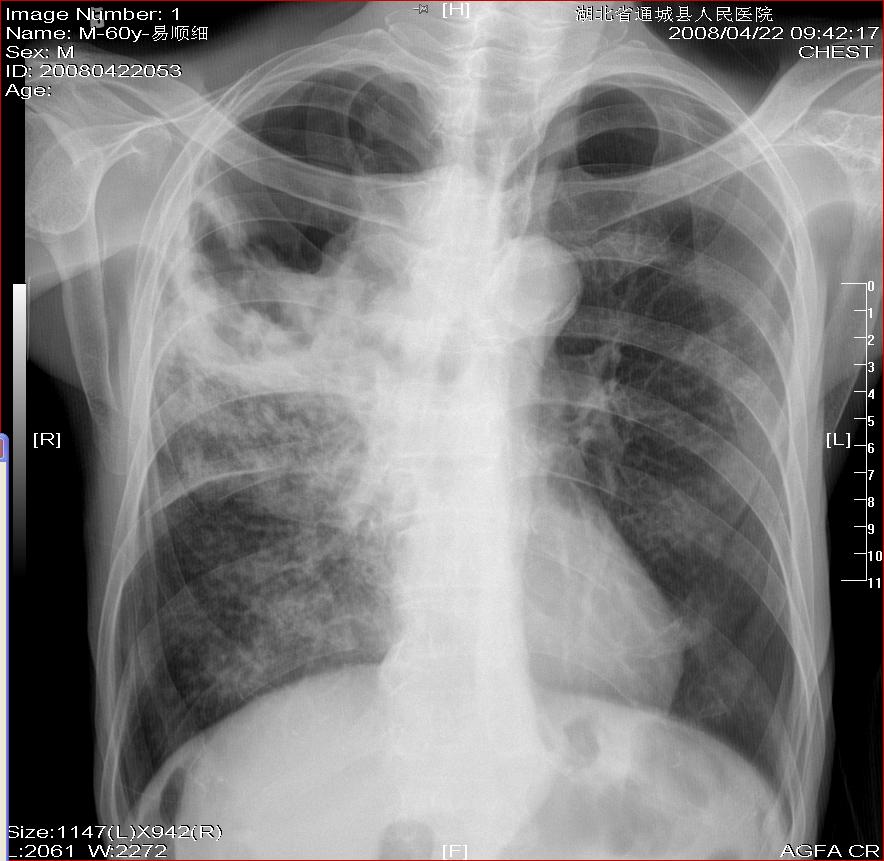

男  60岁  自述:进行性消瘦  畏寒  咳嗽  偶咳粘稠‘黑’色痰  食欲下降一月余。不烧 无盗汗。

右肺tb

右肺中央型肺癌并阻塞性肺炎,慢支肺气肿。主动脉硬化,肺心待排,建议ct检查。

考虑右肺干酪性肺炎并双肺播散

1)右上肺继发性肺结核伴空洞形成,两肺支气管播散。2)主动脉结钙化。

胸片有胸片的局限性,此种病例最好做ct检查,排除肺ca,另右上肺可能有肺大泡

1)右肺继发性肺结核,两肺支气管播散

2)右上肺损毁?

1)右上肺继发性肺结核伴空洞形成,两肺支气管播散。

支持.未见明确肿块.

考虑右肺干酪性肺炎并双肺播散,建议ct检查。

为什么老没侧位片,不好排除肿块.但下肺野也有小片影,多考虑tb播散